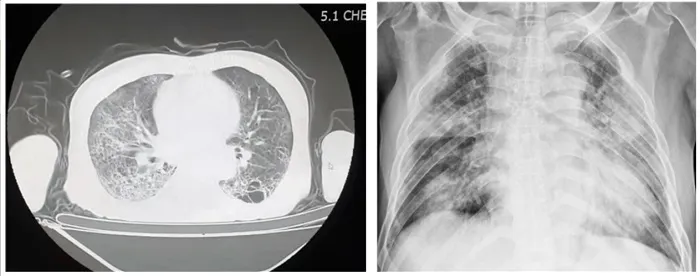

2021년에 경북대학교에서 진행한 완지차 대상 설문조사에서 응답자 965명 중 91%(879명)가 최소 1개 이상의 후유증을 겪고 있다고 응답했다. 그리고 코로나19바이러스 감염증에서 가장 우려가 되는 부분은 바로 폐손상이다. 독감이나 감기로 인해 직접적으로 폐손상이 발생하는 경우는 거의 없다. 그러나 코로나19바이러스는 바이러스 자체가 직접적으로 폐의 손상을 유발하는 것으로 나타났다.

특히나 중증으로 발전한 코로나19바이러스감염증 환자들은 대부분 폐의 손상으로 인해 사망에 이른다. 코로나19바이러스가 폐를 박테리아나 세균으로 부터 보호하는 대식세포에 영향을 줘 폐의 염증을 악화시키는 것으로 밝혀졌다. 이는 일반적인 인플루엔자로 인한 독감이나 감기에서는 볼 수 없는 현상이다.